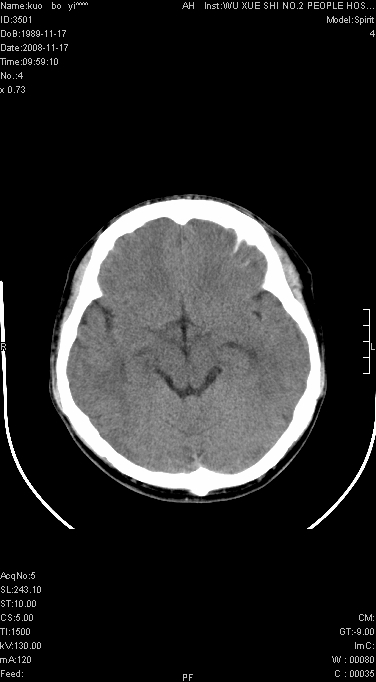

还是考虑原发脑胶质瘤,梗塞缺血水肿的低密度要同时累及皮、髓质并要符合动脉供血的区域分界特点,本例强化后见瘤体结节及向周围浸润生长的瘤血管都强化了,水肿广泛呈指状,占位效应使同侧脑皮质受压变薄、脑沟消失但因实质性的瘤体尚小所以中线无明显移位。不知各位同意这样分析吗?(转移瘤多为多处病灶)

不符合脑梗塞表现。

不像脑梗死,低密度区中心,有一密度增高边界清楚的,近脑组织密度的病灶.建议进一步强化及肺和肝等重要脏器检查.

在北京天坛医院治疗考虑寄生虫感.明显好转